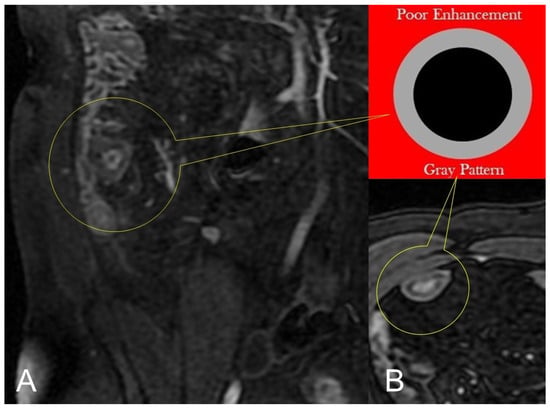

In CD, segmental bowel wall mural hyperenhancement represents the pathological tissue that at contrast-enhanced MRE is revealed as increased mural signal intensity in a small bowel’s segment compared with the normal adjacent intestinal tract [5]. Mural hyperenhancement can be asymmetric (in a small bowel loop, it could involve the mesenteric border more than the antimesenteric one), stratified (bilaminar or trilaminar inner-wall hyperenhancement or halo sign), or homogeneous (evenly distributed over the entire bowel wall). Submucosal edema, granulation tissue, intramural fat accumulation, fibrosis, or inflammatory infiltration may contribute to stratified enhancement (Figure 3 and Figure 4). Bowel wall enhancement evaluation is correctly depicted in the enteric phase (45–50 s after the intravenous contrast material injection begins) and/or in portal venous phase (60–70 s after the intravenous contrast material injection begins). Furthermore, we consider also that endoscopy and histopathological examination clearly show the absence of mucosa in the affected intestinal segments, so the term “mucosal hyperenhancement” is incorrect when the stratified enhancement pattern is expressed and should not be used. Finally, it must be underlined that the segmental bowel wall mural hyperenhancement is a sensitive but non-specific sign of CD, and therefore it must always be contextualized in the general framework of interpretation [6].

Lack of layered or homogeneous enhancement can be related to fat ((B), axial FIESTA) image, or fibrosis parietal deposition, with poor enhancement and gray pattern on contrast-enhanced fat-suppressed T1-weighted image ((A), coronal image).

In chronic disease, there is a fat deposition in the submucosal layer that appears as hypo-intensity in the thickness of the intestinal wall on T2-weighted images with fat saturation (Figure 4B).

During subacute transmural inflammation, the thickened and fibrotic bowel wall exhibits diffuse and homogeneous contrast enhancement, and the mild mucosal enhancement with hypo-intensity of the deep layers suggests fibrotic condition [19].

Thickening throughout the intestinal loop circumference might be eccentric (asymmetric) or circumferential (symmetric) depending on the type of involvement (Figure 16B,C) [29,30]. According to the length of the pathological bowel tract, thickening can be focal, segmental, or diffuse. Bowel thickening is defined as focal when the pathological tract is shorter than 5 cm in length (Figure 17A); segmental thickening refers to 6–40 cm in length of thickened small bowel (Figure 17B), while it is considered diffuse when a large amount of small bowel loops (>40 cm) is affected (Figure 17C) [29,30]. After contrast-medium injection, various patterns of wall enhancement can be described: stratified, white, and gray [30]. Contrast enhancement is classified as stratified when there is hyperintensity of the inner layer (muco-sa), hypointensity of the intermediate layer (submucosa), and hyperintensity of the outer layer (muscle and serosa layers); this is caused by mucosal hyperemia and submucosal edema. If stratified contrast enhancement is associated to fat deposits in the submucosal layer, it is called “fatty halo” sign [30,31].

The white pattern is caused by intestinal wall enhancement that is more than or equal to vein enhancement of the same degree. The gray pattern (diminished or mild enhancement of the bowel wall) occurs when the enhancement of the bowel wall is similar to muscle attenuation on a contrast-enhanced exam [30].